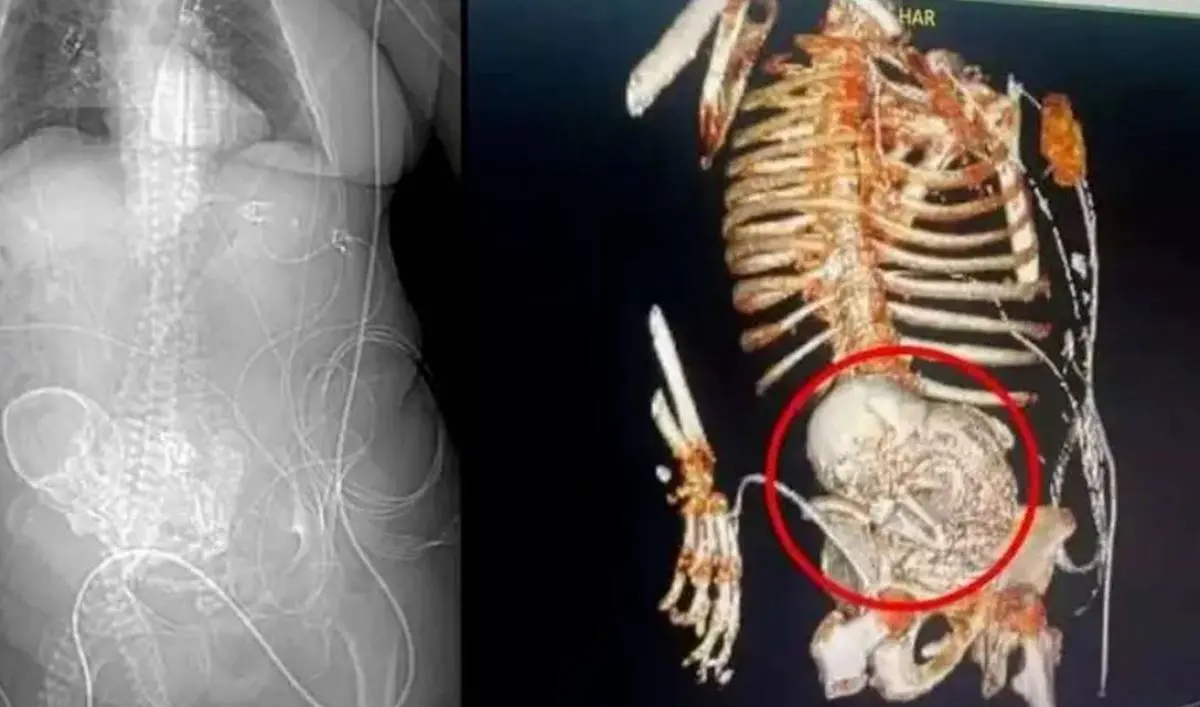

De acuerdo a los médicos, la brasileña de 81 años habría quedado embarazada hace décadas, cuando tenía entre 40 y 50 años, pero el óvulo se fertilizó fuera del útero, por lo que deriva en la muerte del feto y su posterior calcificación.

La mujer, que toda su vida se rehusó a visitar médicos y optar a la medicina natural, solo se enteró de que llevaba en su cuerpo un feto calcificado luego de que sufrió una caída y para atender los malestares le practicaron una tomografía.

Tras hacer el extraño descubrimiento, los médicos decidieron realizarle una cirugía, pues a consecuencia de la caída que sufrió más la presencia del feto calcificado se le había desarrollado una grave infección.